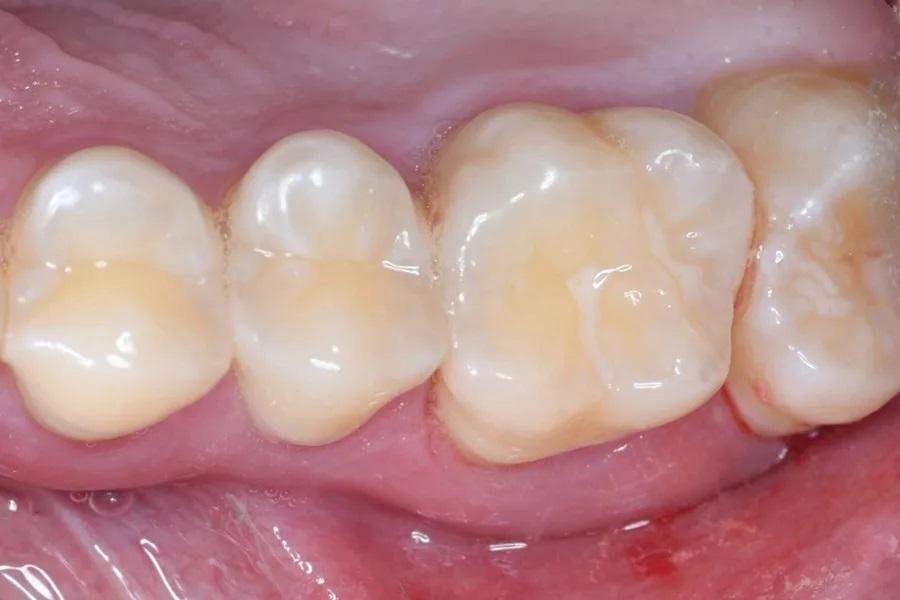

Фото 1 и Фото 2. Внеоральный осмотр выявил легкую болезненность в левом ВНЧС; интраоральный осмотр показал тонкий фенотип десны, локализованную рецессию десны и потерю клинического прикрепления. Предоперационные вестибулярный (Фото 1) и окклюзионный (Фото 2) виды показали воспаление десны, минимальную рецессию и глубину зондирования 12 мм с вестибулярной поверхности зуба № 2.6.